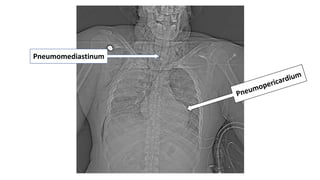

Gunshot Wound

To The Neck…

Injury To The Trachea & Esophagus

Pneumomediastinum

• Pneumomediastinum/pneumopericardium